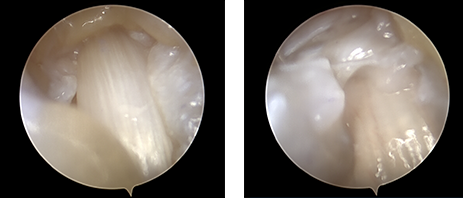

기존의 약 1~2cm 피부를 절개하였던 개방형 유리술과 다르게 미세내시경 유리술은 부분 마취하에 2mm 미세내시경을 수직 및 수평 피부절개 없이 작은 내시경포털만을 이용해 병변에 접근합니다. 그 후 주변조직 손상없이 손가락 힘줄의 뚜껑부분인 활차만을 선택적으로 절개해 터널을 넓혀주는 유리술을 진행합니다. 수술시간은 5분 이내로 짧아졌으며, 내시경을 보면서 수술을 진행하기 때문에 안전성 또한 더욱 높아졌습니다.